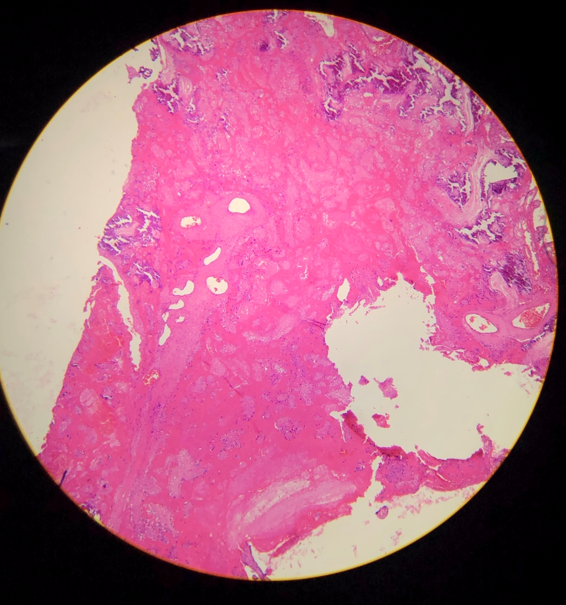

Órgão: Placenta.

Descrição: A lâmina apresenta uma placenta com áreas de necrose na face materna (decídua) com massa amorfa e eosinofílica, acompanhada de inflamação e há ausência de núcleo na área de necrose.

Diagnóstico: Infarto Placentário.